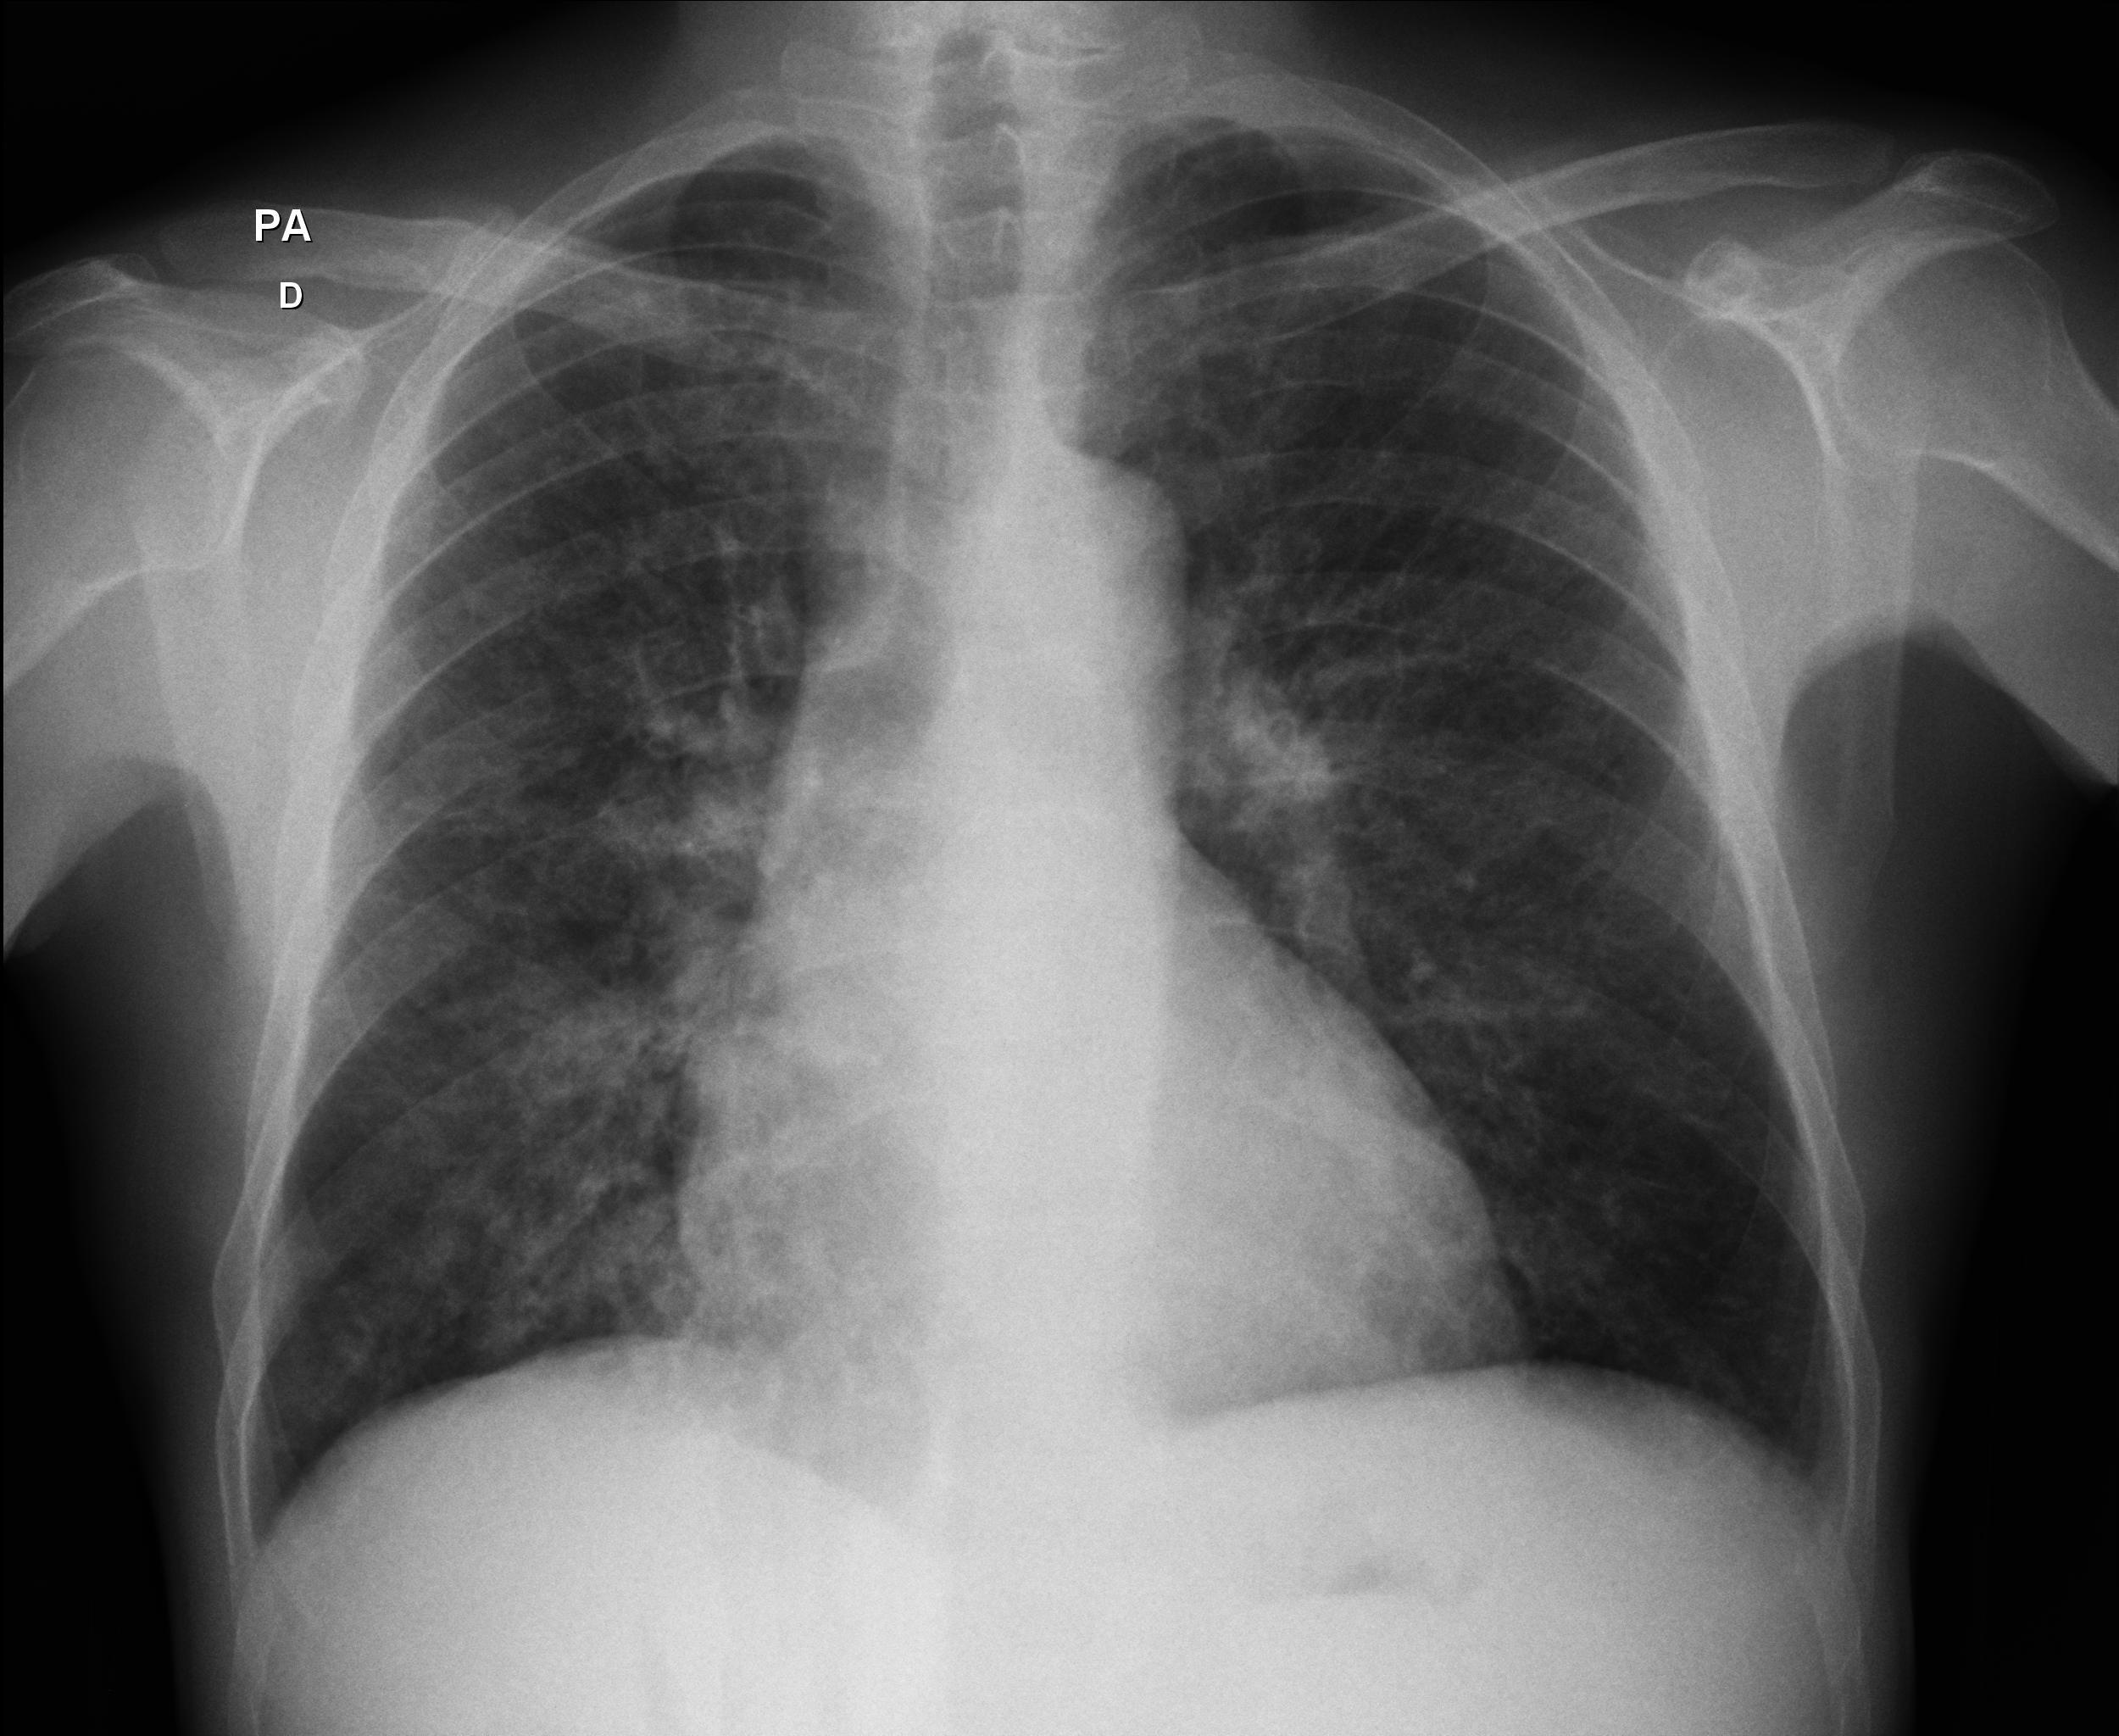

Caso relatado na Reunião de Discussão de Casos Clínicos do Hospital Universitário Prof. Polydoro Ernani de São Thiago, iniciada pelos Profs. Jorge Dias de Matos, Marisa Helena César Coral e Rosemeri Maurici da Silva, em julho de 2017. No dia 14 de junho de 2018, no auditório do HUPEST, realizou-se a apresentação e discussão do caso cujo registro é apresentado a seguir. Trata-se da discussão de onze casos em radiologia torácia, de forma interativa com a plateia, e assim ocorre também neste artigo.